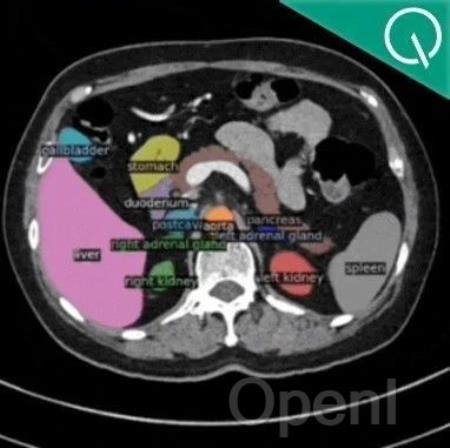

BiomedParse团队 投稿量子位 | 公众号 QbitAI用AI大模型一键解析MRI、CT和病理学等九大生物医学成像模式。

还可一次性同时分割和标记所有感兴趣的生物医学对象:

而BiomedParse,通过文本驱动图像解析将九种医学成像模式整合于一个统一的模型中,联合预训练处理对象识别、检测与分割任务。

无论是影像级别的器官扫描,还是细胞级别的显微镜图像,BiomedParse都可以直接利用临床术语进行跨模式操作,为科学家和临床医生提供了更统一、更智能的多模式图像解析方案。